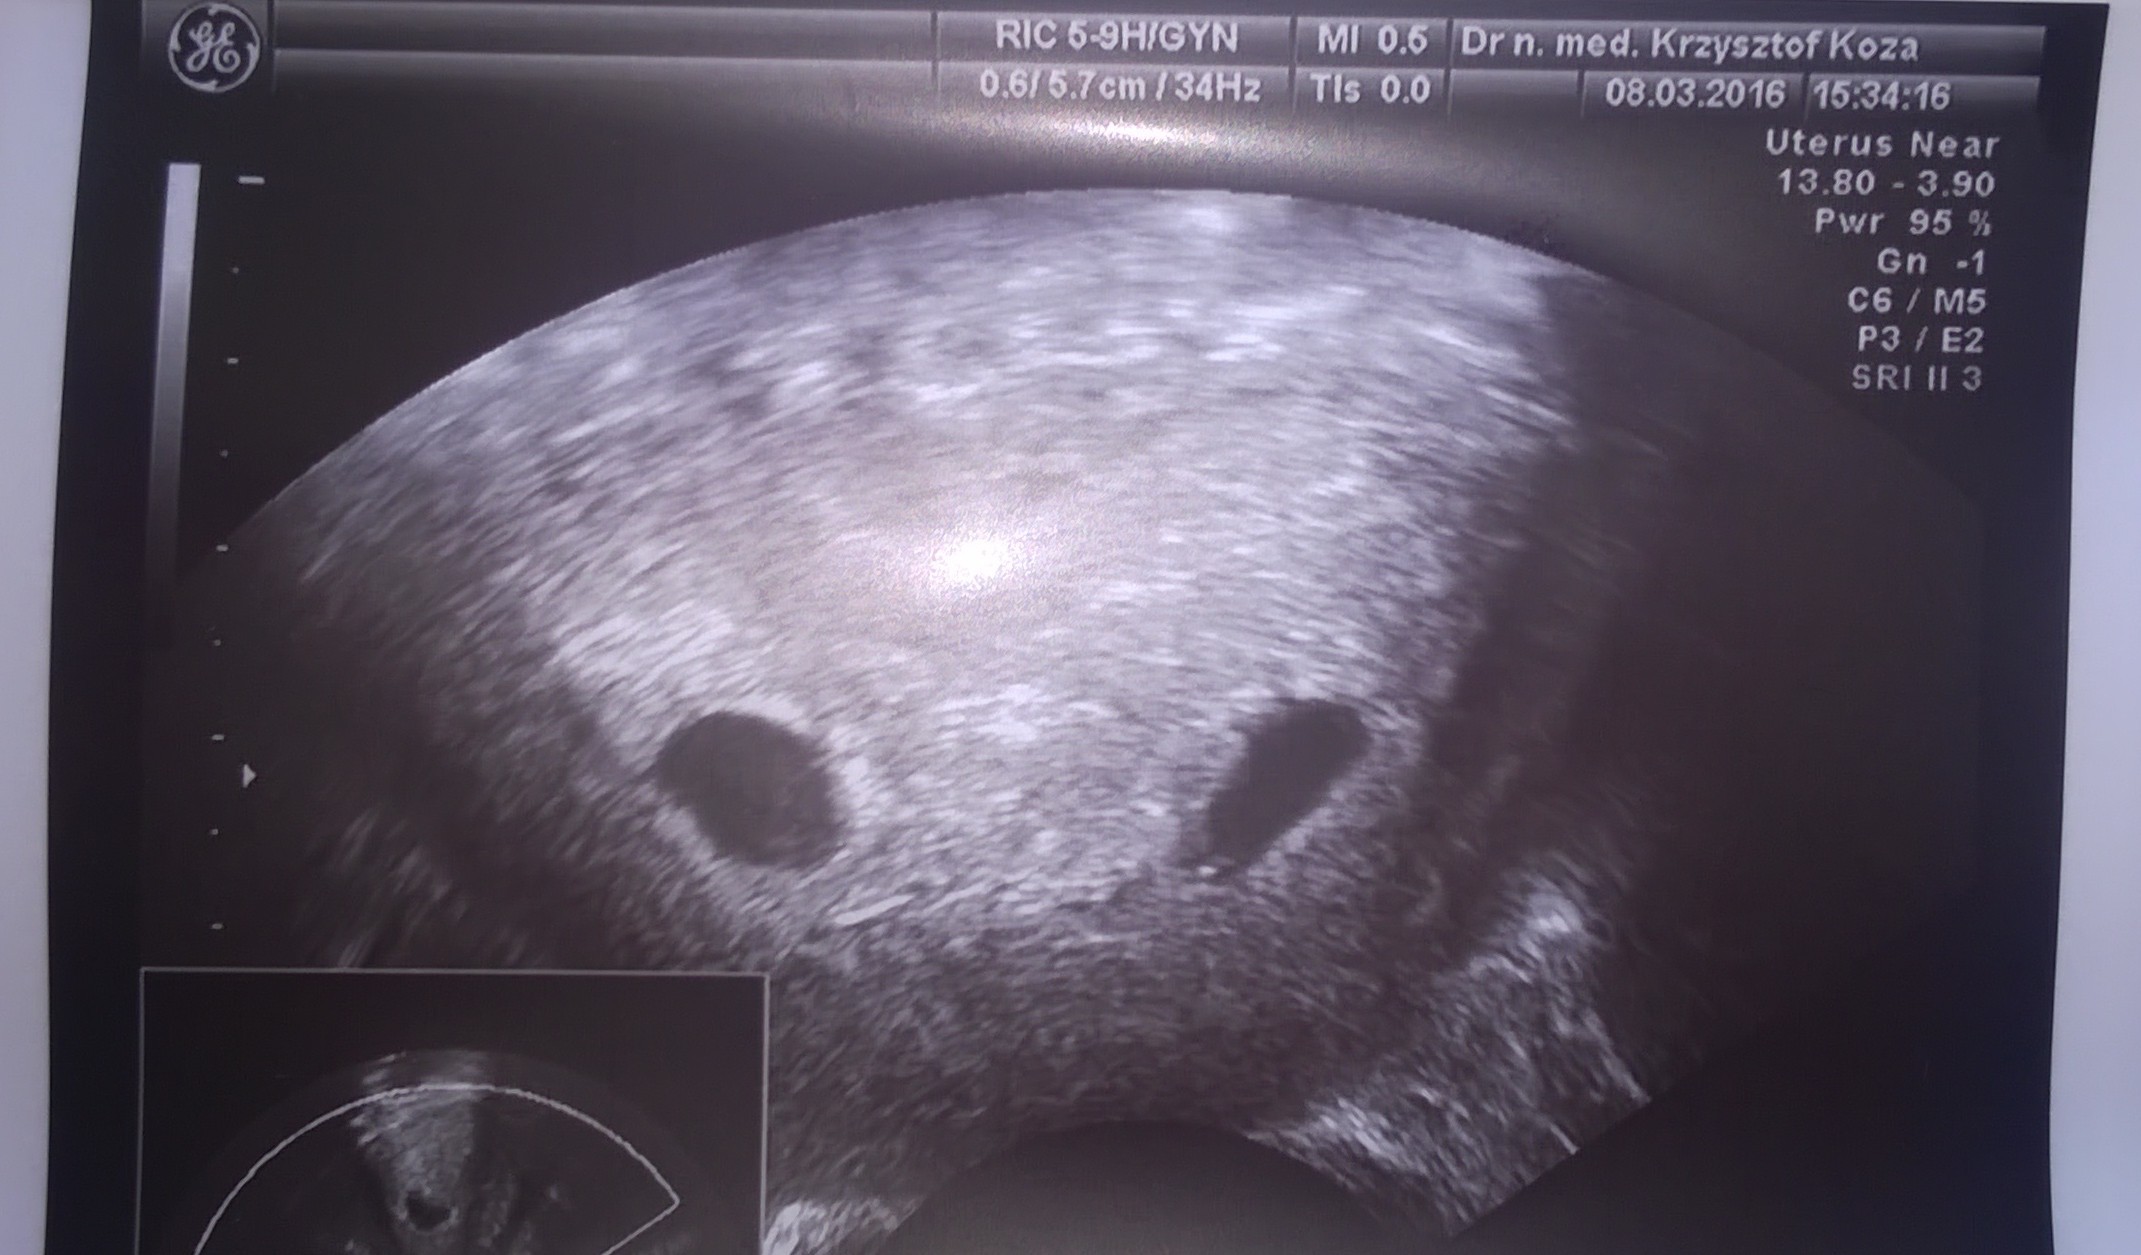

A mnie olśniło, ze nie pokazałam Wam mojego zdjęcia. Gapa ;) Zabieram sie za wylegiwanie i czytanie zaległości ;)

Załączniki

• WP_20160308_001.jpg

WP_20160308_001.jpg

404,9 KB · Wyświetleń: 101